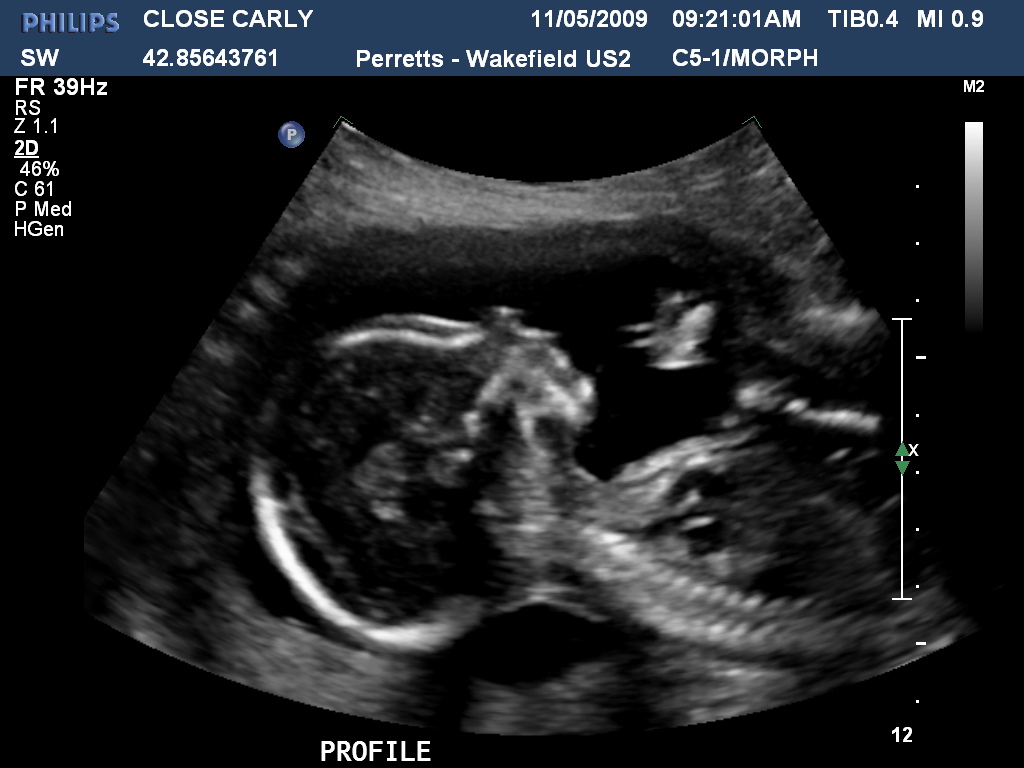

Wow how time flies! Carly is now 159weeks pregnant and now definately showing. Last week we had the first real scan and got to see hands and feet, the bub was quite active and gave the radiologist a hard time! Below are a few photos of both the bub and the expectant Mum to be!